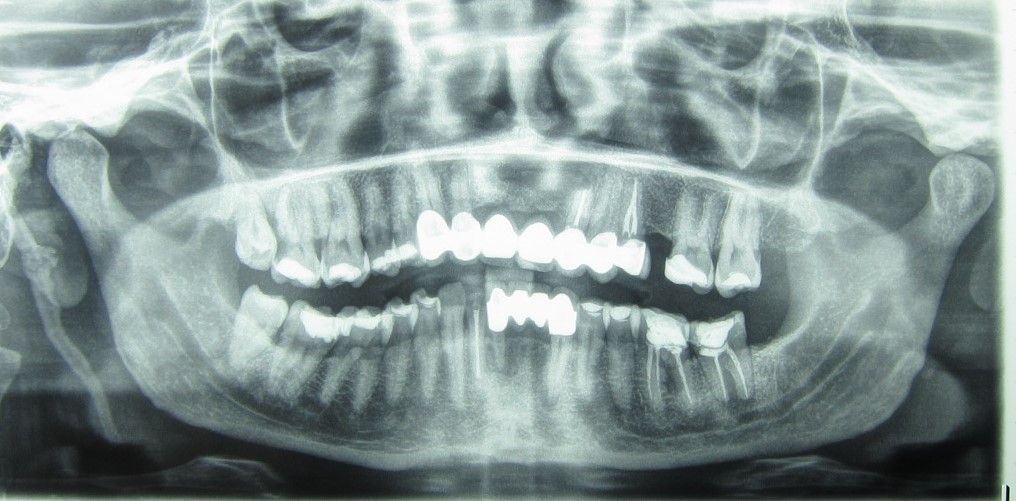

Απονευρωμένα δόντια, κυρίως με ελλιπή απονεύρωσή είτε στο μήκος είτε στο πάχος, μπορούν να εμφανίσουν φλεγμονή γύρω από τις ρίζες τους. Η φλεγμονή προκαλεί πόνο, πρήξιμο ή συρίγγιο στην περιοχή της ρίζας του απονευρωμένου δοντιού.

Στις περιπτώσεις αυτές η ενδεδειγμένη αντιμετώπιση είναι η επανάληψη της απονεύρωσης από ειδικό ενδοδοντιστή ή έμπειρο στις απονευρώσεις γενικό οδοντίατρο.

Έαν η επανάληψη της απονεύρωσης είναι αδύνατη για διάφορους λόγους και εφόσον το δόντι έχει αρκετή οστική στήριξη ώστε να μπορεί διατηρηθεί, τότε προτείνεται η ακρορριζεκτομή.

Η ακρορριζεκτομή αφορά την αφαίρεση του άκρου της ρίζας ενός απονευρωμένου δοντιού που συνδυάζεται με απόξεση και χειρουργικό καθαρισμό της περιοχής γύρω από την οδοντική ρίζα.